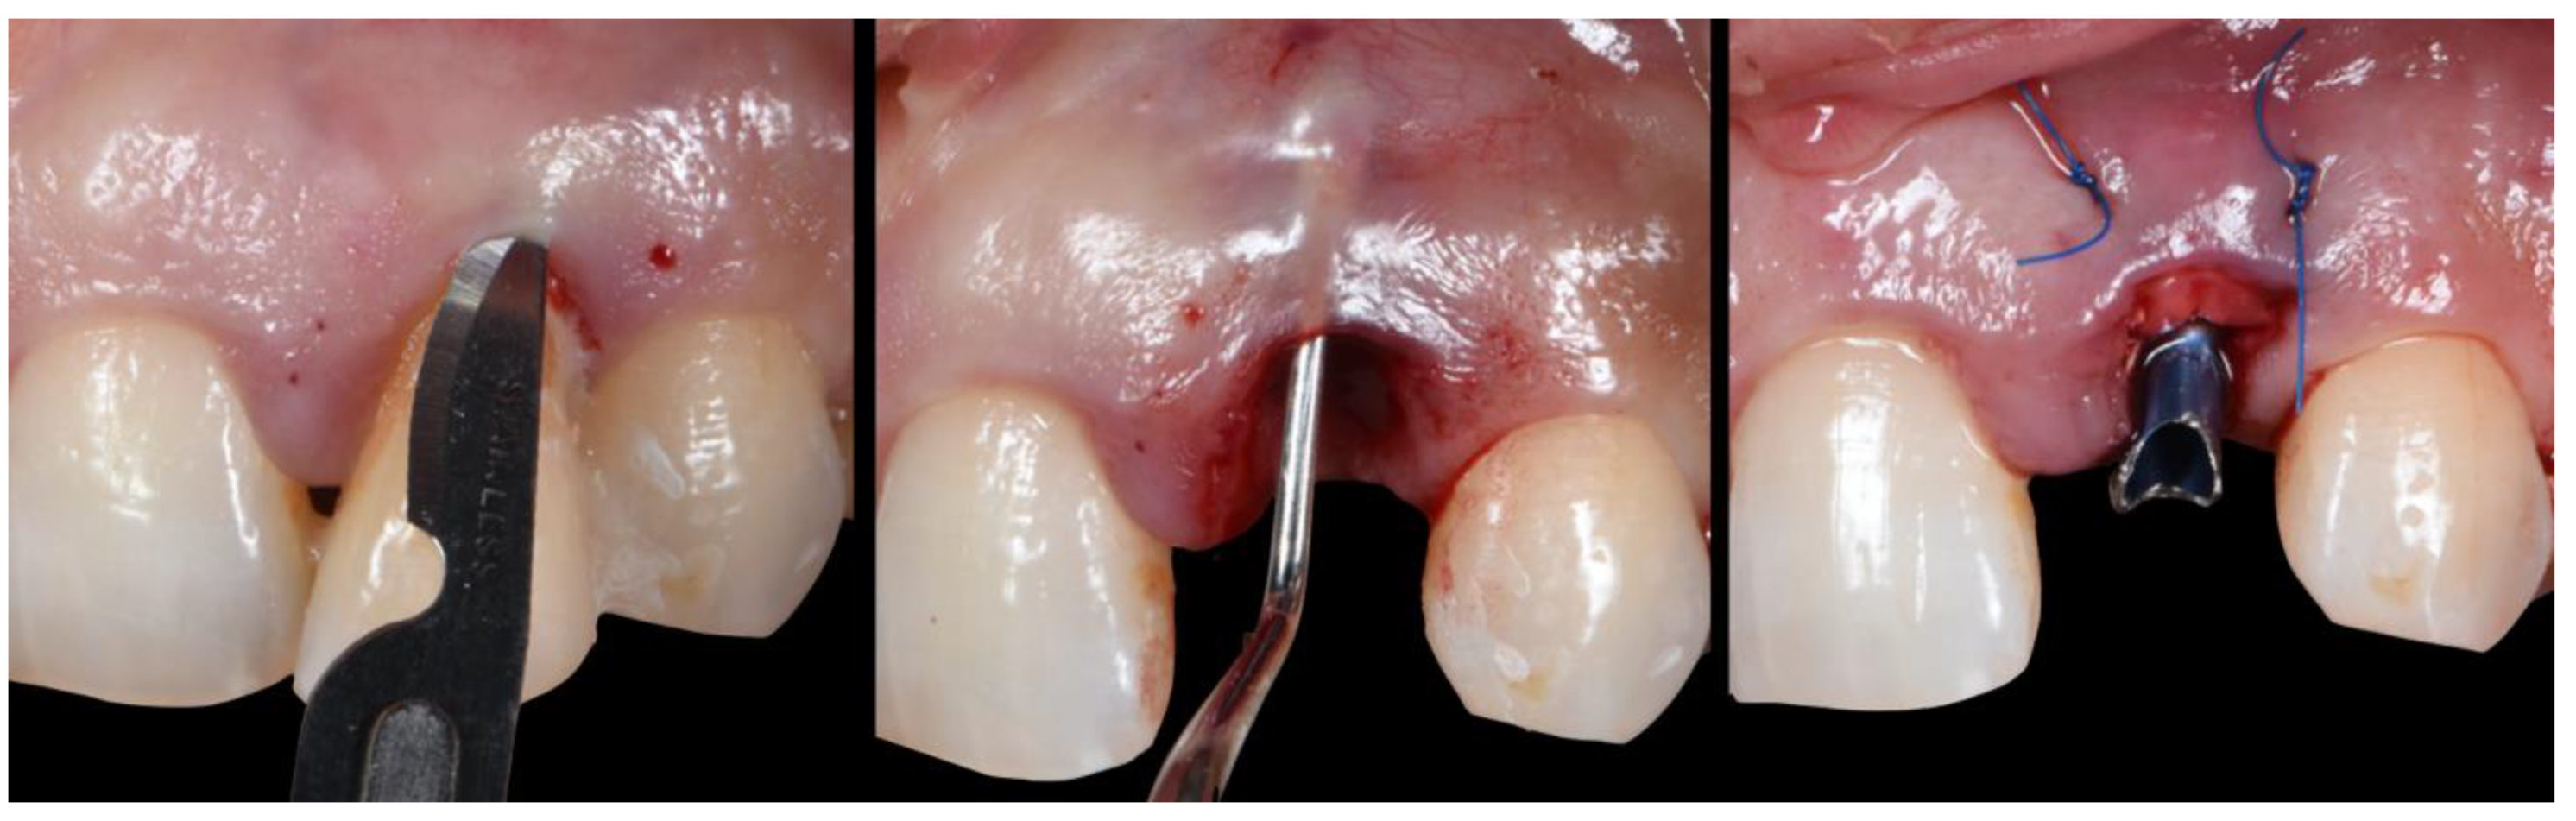

- (A)

- Extraction socket presentation, where the red line represents the supra-periosteal pouch flap.

- (B)

- Three-dimensional implant positioning, where different locations of the implant axis can achieve the desired location of the platform and neck of the implant.

- (C)

- Fits abutment selection, where the shoulder is located 0.5 mm apically to the cervical gingival margin.

- (D)

- Membrane adaptation, being in contact with the internal wall of the socket.

- (E)

- Bone replacement graft BRG introduction into the available space present within the socket, occupying both the soft and hard tissue zones present below the abutment’s shoulder.

- (F)

- Membrane adaptation and suturing with vertical mattress sutures.

- (G)

- Temporary prosthesis delivery, where the cervical margin is located supra-gingivally and comprises a 90′ emergence angle in relation to the abutment.